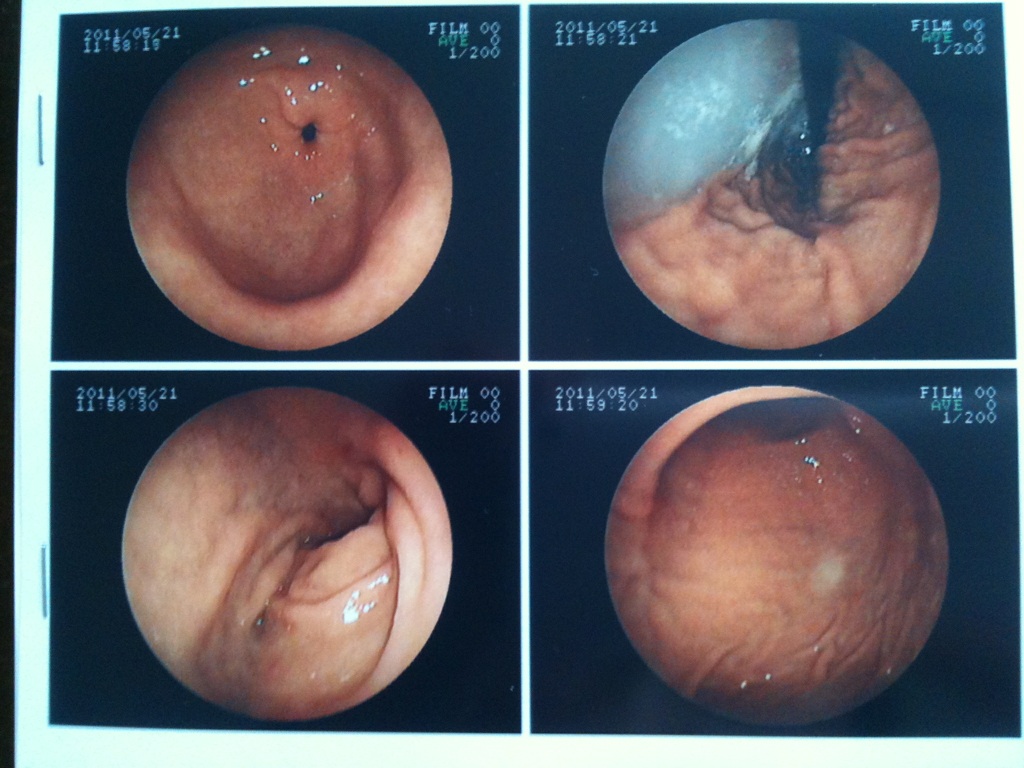

今日、胃カメラの検査を受けてきた。

結果、異常なし。 よかったぁ(^。^)y-.。o○ キレイな胃らしい↓ 白いのは検査前に飲んだ液体。 写真くれるんだね。 びっくりした。 かかりつけ医に鼻は楽だからと勧められ、鼻で予約してもらったけど、 以前、鼻からやった後輩に聞くとしんどかったとのこと。 私は5.6年前に口から胃カメラを飲んだことはあるけど、 バリウム検査の方がしんどくて、胃カメラの記憶が薄れていた。 口の方がいいような・・・。 との思いを抱えながら病院へ。 鼻で準備を始めたけど、 どうやら私の鼻の奥は細かったようで、口に変更した。 反対側の鼻からするかと言われたけど、 鼻から液体の麻酔を入れるのも結構苦しくて、 またやるのかと思うと嫌だったし、 左右で違うと言われたけど、 鼻の大きさってそう変わらんやろ!!とも思った。 ま、何より、自転車が撤去されるのかが心配で、 一刻も早く検査を終わらせて帰りたかったのが一番の理由なんだけどね^_^; 口からの検査も想像以上にしんどかった(>_<)。 何度も『オェオェ』言ってたわ。 今回は忘れないためにも記憶に残しておこうと思った。 あと、検査料が9000円もしてびっくりした。 後輩に聞いたら、5000円ぐらいだったと思いますって言ってたのに。 すぐ、後輩に苦情のメールをしたよ(*^_^*) 胃が痛かったのは、心配しすぎやったんかな?! |